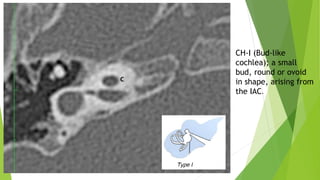

a- CH-I (Bud-like cochlea)

The cochlea is like a small bud, round or ovoid in shape,

arising from the IAC.

Internal architecture is severely deformed; modiolus and

interscalar septa cannot be identified.

CH-I (Bud-like

cochlea); a small

bud, round or ovoid

in shape, arising from

the IAC.

a- CH-I (Bud-likecochlea) The cochlea is like a small bud, round or ovoid in shape, arising from the IAC. Internal architecture is severely deformed; modiolus and interscalar septa cannot be identified.

• 42.

CH-I (Bud-like cochlea); asmall bud, round or ovoid in shape, arising from the IAC.